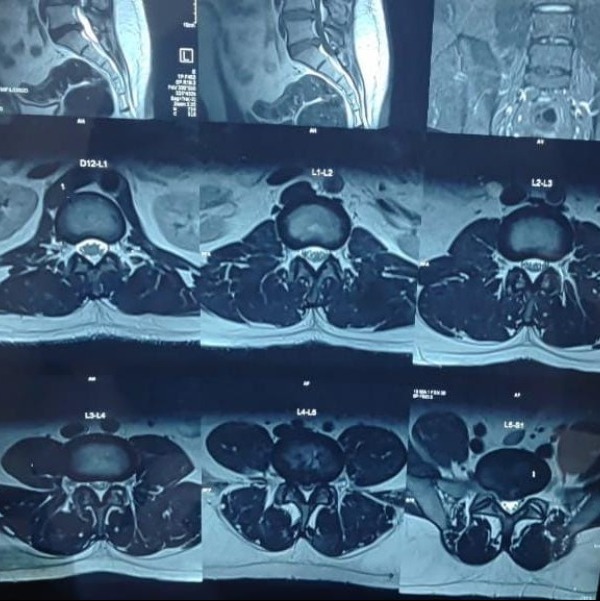

L4-5 , L5-S1 PID with Bilateral LL radiculopathy with bilateral EHL, EDL weakness with Bladder involvement treated with L4-5 and L5-S1 decompression and L4-5 Posterior lumbar interbody fusion !